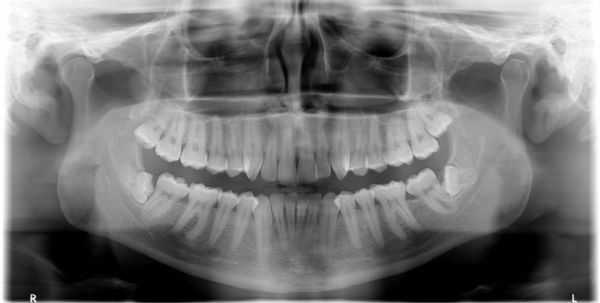

Слизистая оболочка в области зуба 1.6 физиологической окраски, безболезненная при пальпации. Сам зуб находится под пломбой, занимающей более 2/3 коронки. На нёбной поверхности зуба виден дефект, широко сообщающийся с полостью зуба, при его зондировании возникает боль. В области дефекта есть пародонтальный карман (пространство между десной и зубным корнем) более 4 мм. Определяется поперечная линия перелома нёбного корня ниже уровня десны на 3 мм. Сам нёбный корень в лунке подвижен, при этом щёчные корни остаются неподвижными. Перкуссия (постукивание) зуба 1.6 болезненная. Противоположный жевательный зуб 4.6 находится под металлической коронкой. Пациент направлен на прицельный внутриротовой рентгеновский снимок зуба. Из-за особенностей прицельной рентгенограммы, наложения структур друг на друга и наличия снимка только в одной проекции линия перелома нёбного корня зуба 1.6 определяется недостаточно чётко. Но в связи с наличием явных клинических признаков, указывающих на перелом корня зуба, принято решение о его удалении.

При первичном визуальном осмотре специалист определяет характер травмы без труда, так как признаки вывиха проявляются достаточно ярко. Но для более детального изучения характера и формы патологии (для оценки состояния челюсти, соседних зубов и иннервации в области повреждённого зуба) стоматолог назначает рентгенологическое исследование: ортопантомографию (ОПТГ) или компьютерную томографию челюсти . Это поможет дифференцировать вывих от иных форм травмы зуба (ушиба и перелома), кроме этого оценить структуру костной ткани, окружающей зуб на предмет трещин и перелома.